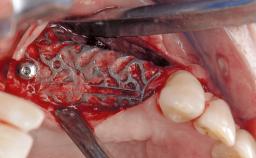

A 72-year-old female patient was referred to the specialist clinic with signs of peri-implantitis associated with implant 14. Two implants (sites 14 and 15) had been in function for three years. The patient was in good general health and was not taking any medication. She was a former smoker (12–15 cigarettes a day for 50 years) but had ceased smoking two years prior to implant placement. Her periodontal condition was stable, with no probing depths above 5 mm and a full-mouth plaque score (FMPS) of 35%.